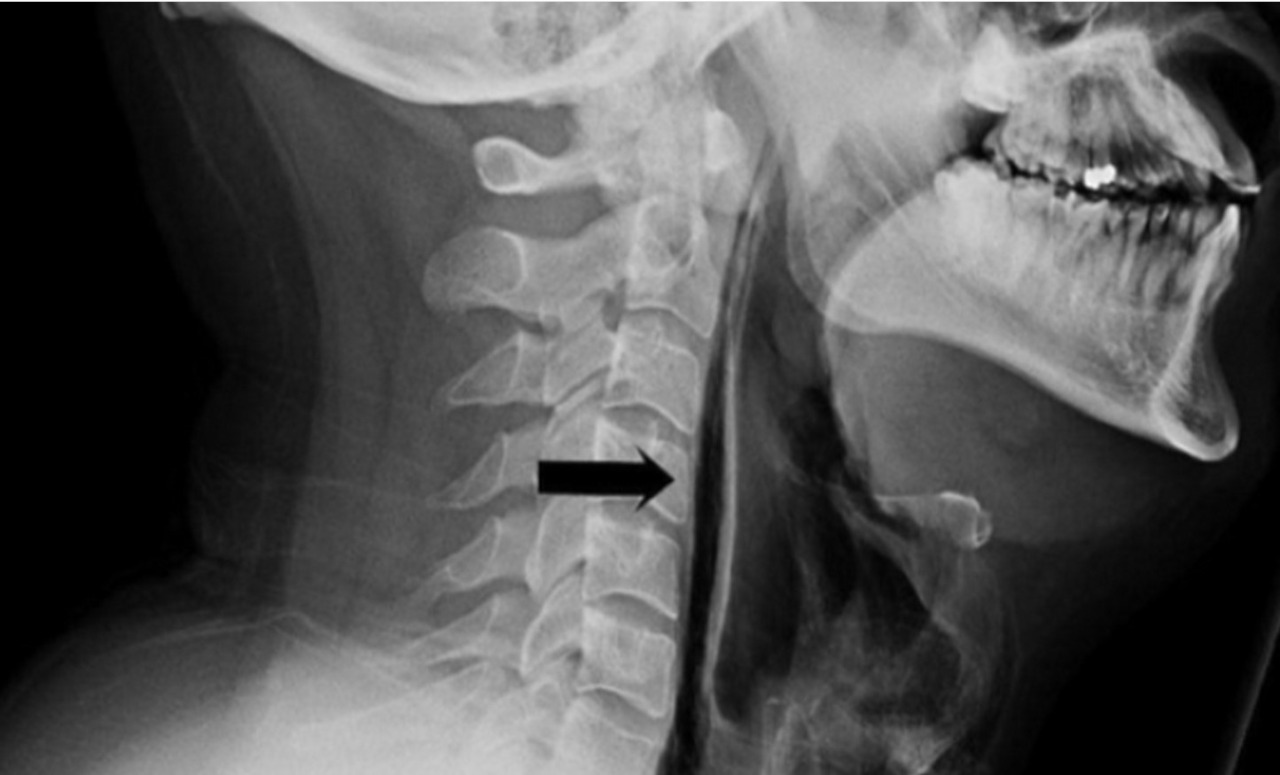

Пациента отправили на рентген — снимок показал спонтанный разрыв пищевода. Травма привела к избыточному скоплению воздуха в шее перед трахеей.